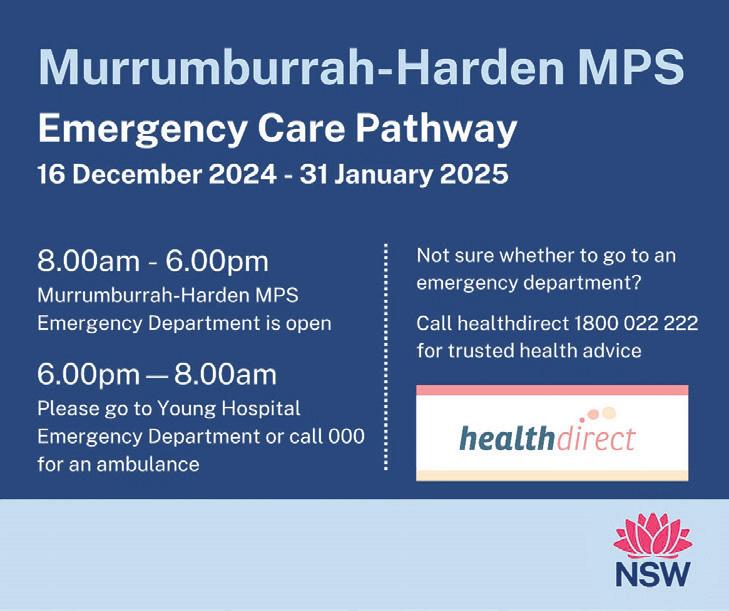

Reminder of Harden MPS ED hours

From Monday 16 December 2024 to Friday 31 January 2025, the Harden Multipurpose Service Emergency department will be open between 8am-6pm.

Patients requiring ED treatment between the hours of 6pm-8am should present to Young Hospital or call 000 for ambulance transport to Young for treatment / care.

If an illness or injury is not life-threatening, visit your GP or call Healthdirect Australia on 1800 022 222, which is a 24-hour telephone health advice line sta ed by registered nurses to provide fast, expert advice on any health issue and what to do next.